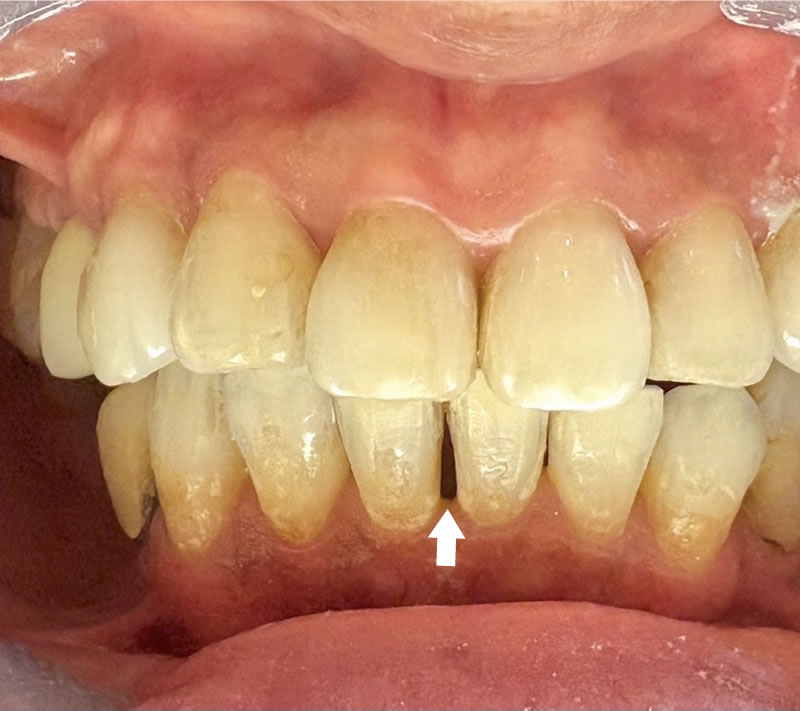

矯正後の60代後半女性で、下の前歯の歯茎下がりの空隙部位に食べものが入ってしまったり唾液が飛ぶから、封鎖したいという主訴でした。

ダイレクトボンディングによる歯の形態修正で足場を作り、ヒアルロン酸をキャリアにした幹細胞由来サイトカインとレーザーによる治癒促進治療による歯周組織再生誘導を同時に併用しました。